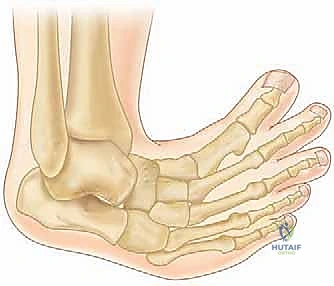

إعادة بناء مقدمة القدم الروماتويدية: دليل شامل للمرضى مع الأستاذ الدكتور محمد هطيف

دليل شامل لإعادة بناء مقدمة القدم الروماتويدية. تعرف على الأسباب، الأعراض، التشخيص، والعلاجات الجراحية وغير الجراحية مع الأستاذ الدكتور محم…